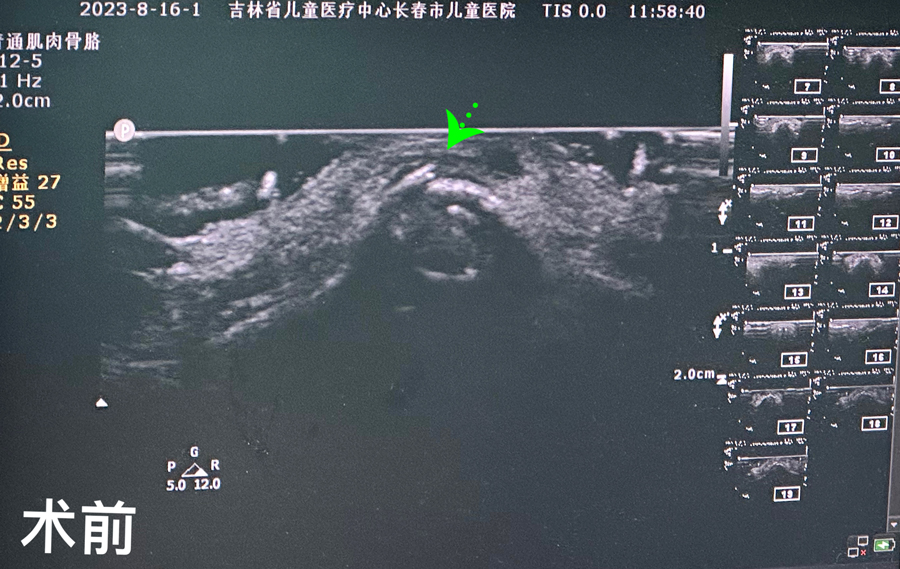

8月15日,彬彬家长在辗转多家医院后,听说蜜桃视频 有鼻骨骨折复位新技术,立即带彬彬赶到医院。此时,距离彬彬鼻骨骨折已经过去一周了。就诊时,彬彬鼻部肿胀已经消退了,能看到他的鼻梁是向左侧偏曲的,妈妈特别希望孩子的鼻梁能恢复到从前高挺、居中的状态。国家儿童医学中心、北京儿童医院耳鼻喉头颈外科常驻专家、蜜桃视频 副院长张薇,蜜桃视频 耳鼻喉科主任李莉萍为其进行鼻部检查,并结合鼻骨CT全面评估后,决定采用超声引导下鼻骨骨折复位术,以实现精准复位,使彬彬的面容不受影响。8月16日,张薇副院长、李莉萍主任及手术室、麻醉科医护人员组成手术团队,为彬彬进行手术。术中,医生在超声引导下应用复位器对游离骨片进行复位调节,使错位的鼻骨重新连续。10分钟后,手术顺利完成,复位后的鼻子外观无畸形。术后,彬彬接受抗感染治疗48小时,情况稳定,顺利出院。

相比较传统凭经验及手感的鼻骨复位术,超声引导下的手术复位能更精准定位到损伤部位,如医生的“透视眼”,实现手术可视化,使医生在术中可准确看到鼻骨断端的对合情况,在“精准、微创、美观”上得到极大优化和提升。患儿无伤口、恢复快。术前和术后鼻骨错位及对合情况B超均有图片准确显示,让家长也能看明白,患儿和家长的心理负担明显减轻不少,改善了就医体验。